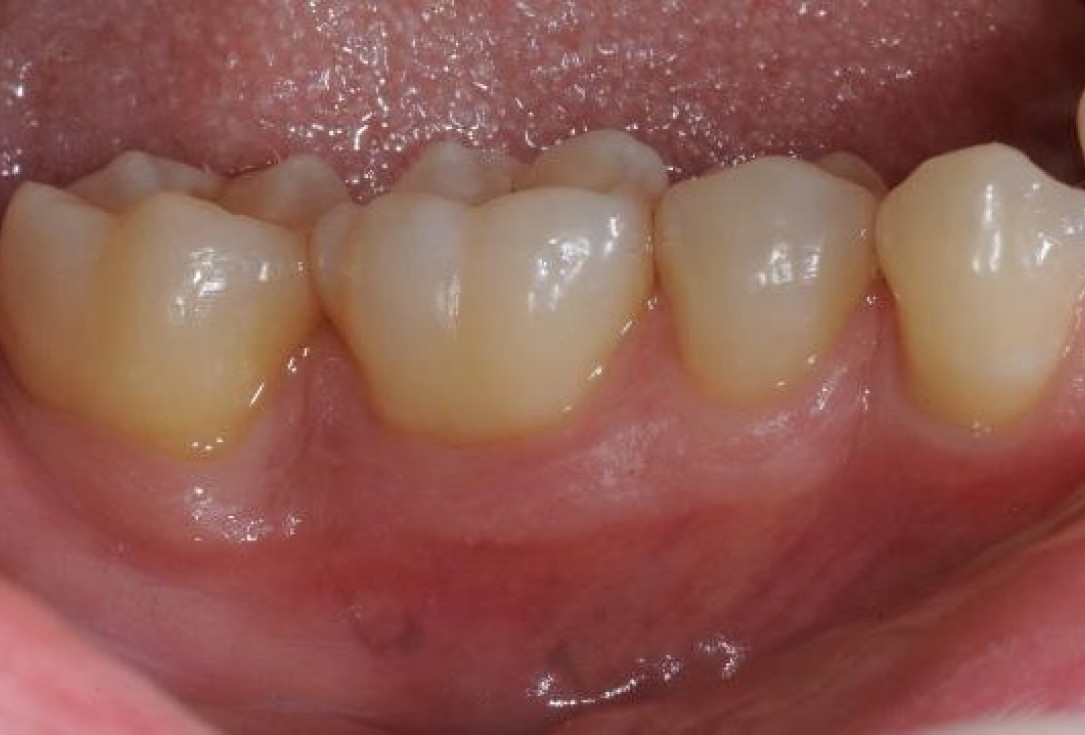

Contained intrabony defect treated using Straumann® Emdogain® - Kasaj

Radiographic view before periodontal regenerative therapy with Straumann® Emdogain®. A deep intrabony defect appeared mesially and distally on the left mandibular first premolar. Pre-surgical probing measured 8 mm. The defect morphology presented as well-contained.